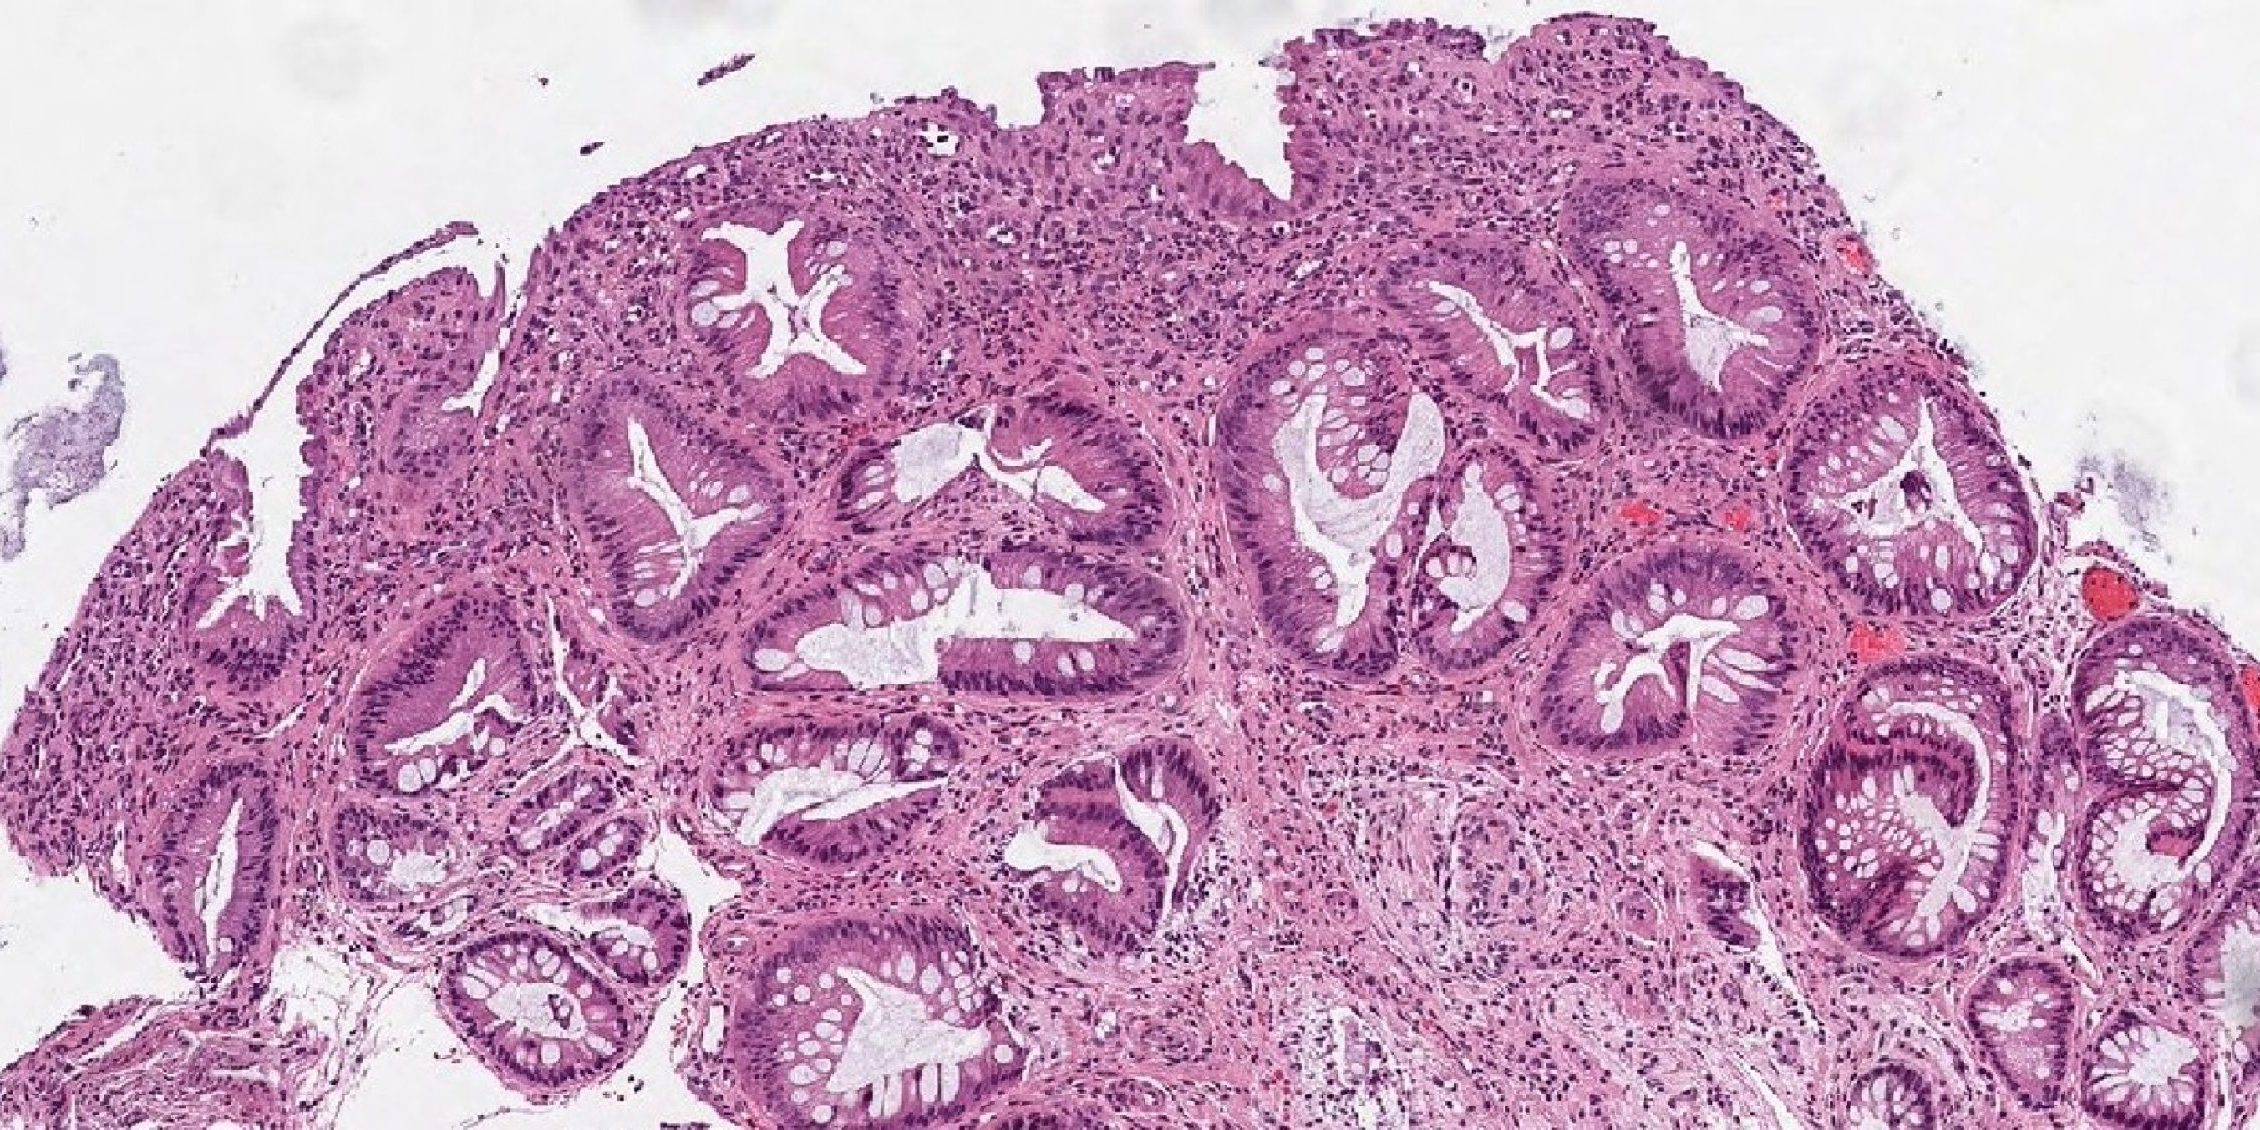

Σύνδρομο μονήρους έλκους του ορθού